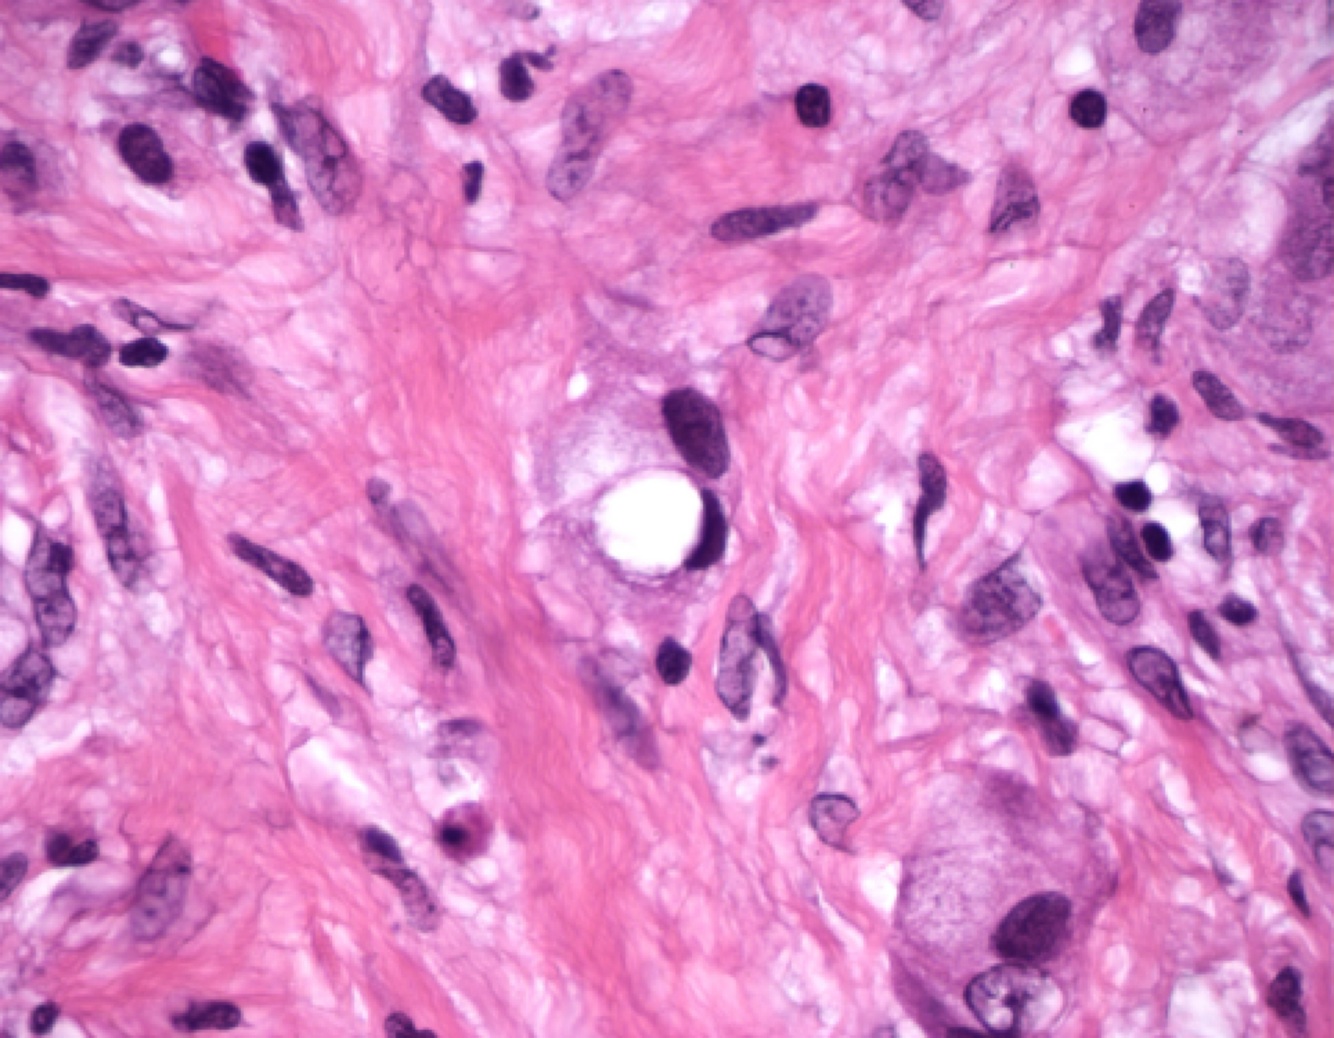

Whipple disease: A biopsy specimen of the lamina propria shows accumulation of macrophages that contain rod-shaped inclusion bodies

Whipple disease: foamy macrophages with periodic acid-Schiff (PAS) positive granules,